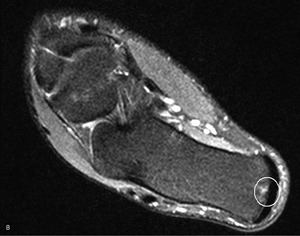

Pacjent, lat 52, zgłosił się do lekarza ortopedy z powodu silnego bólu w okolicy prawej pięty, który wystąpił nagle poprzedniego dnia podczas treningu piłki nożnej. Pacjent uprawia sport regularnie. Do tej pory nie cierpiał z powodu żadnych dolegliwości bólowych tej okolicy, a początek bólu nie był związany z bezpośrednim urazem. Podczas badania stopy okolica ścięgna Achillesa (piętowego) była obrzęknięta i bolesna, ruchy czynne w stawie skokowym znacznie ograniczone. Stwierdzono brak palpacyjnej bolesności w okolicy kostki przyśrodkowej i bocznej z zachowaną stabilnością w ruchach na boki.

Obrzęknięta okolica ścięgna Achillesa wraz z nagłym początkiem dolegliwości wskazuje na jego zerwanie. Niemniej możliwość wykonywania czynnych ruchów w stawie skokowym, nawet w niewielkim zakresie, przemawia za innym rozpoznaniem. Nie występuje też wyczuwalna luka w ścięgnie, jednak może być ona maskowana obrzękiem tej okolicy. Zapalenie kaletki głębokiej ścięgna Achillesa również może wywołać podobne objawy. Często wiąże się ono z występowaniem wyrośli kostnej na kości piętowej (deformacja Haglunda), która drażniąc kaletkę, wywołuje jej stan zapalny. Do złamań zmęczeniowych kości piętowej najczęściej dochodzi u żołnierzy oraz sportowców, którzy biegają długie dystanse po twardym podłożu. Jednakże w tym wypadku jest to mało prawdopodobne rozpoznanie, ponieważ pacjent może stanąć na pięcie oraz nie ma krwiaka i obrzęku tej okolicy.